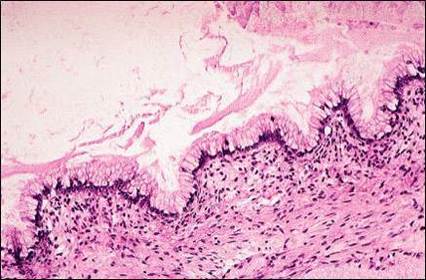

Qual o nome da alteração que pode ser observada na seta? Surge em qual contexto? Cisto de Naboth. Metaplasia Escamosa.